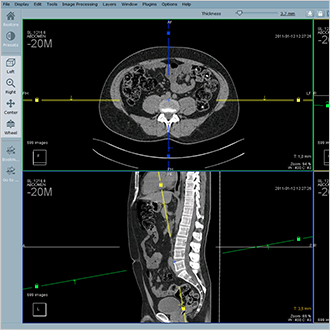

Hyper.PACS

HyperPACS ist ein Universal-PACS für alle medizinischen Bilder, sowohl DICOM als auch Nicht-DICOM. Es basiert auf drei Hauptsäulen: Tempo, Stabilität und Sicherheit.

Hyper.PACS ermöglicht den schnellen Datenzugriff und hundertprozentige Datensicherheit. Die Schnittstelle wurde in Zusammenarbeit mit Benutzern so entwickelt, dass es auf intuitive Weise Diagnose, Visualisierung und Telemedizin ermöglicht.

Der Workflow ist mit Hanging Protocols, Verlaufsanzeige und Sitzungsparken optimiert. Zusätzliche Module wie orthopädische Planung und der Bilderaustausch für die Telemedizin sind verfügbar.